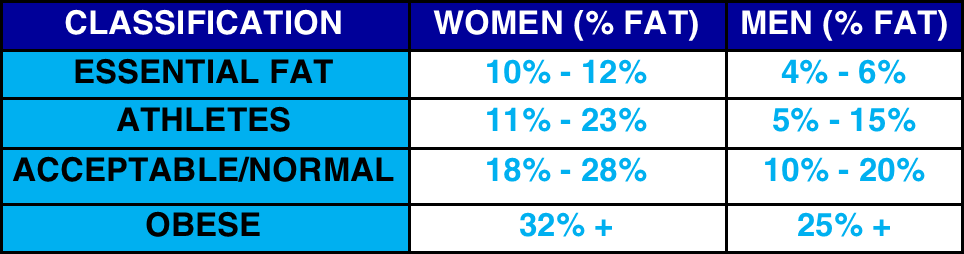

BODY COMPOSITION

MEASUREMENT OF FAT, MUSCLE AND BONE MASS IN YOUR BODY. PER REGION AND TOTAL BODY RESULTS IN GRAMS AND PERCENTAGES PRODUCED.